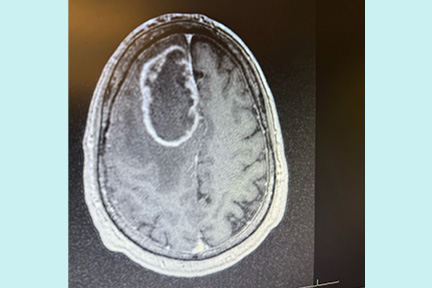

At Memorial Regional Hospital, imaging revealed the cause, a brain tumor. Scott describes that moment as surreal. He was confused, exhausted, and unsure what would come next.